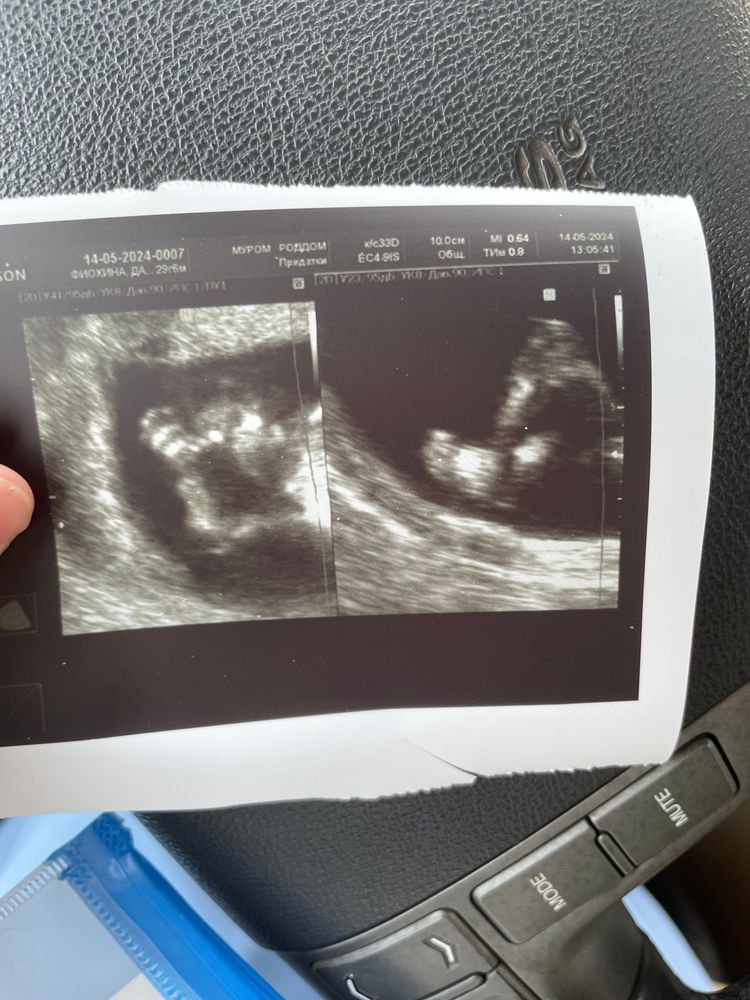

1 скрининг❤️

Поздравляю)) я сегодня тоже 1 скрининг прошла🥰 По узи все отлично, надеюсь и кровь хорошая придет😁

Дарья, нет, у нас на таком сроке не смотрят, да и к лучшему. Сходу попозже и попрошу в конверт написать, потом устроим гендер пати🤗